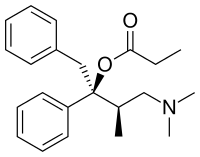

Phenalkoxams

- Dextropropoxyphene (propoxyphene)

- Dimenoxadol

- Dioxaphetyl butyrate

- Levopropoxyphene

- Norpropoxyphene

- Pyrroliphene

Structures

| Phenalkoxams | ||||

|---|---|---|---|---|

Dextropropoxyphene |

|

|

|

|